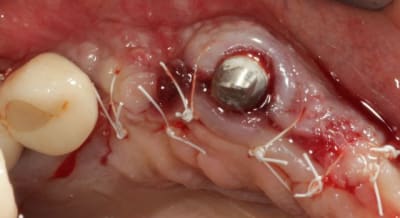

Grosse perte osseuse au niveau de la 23, ROG avec Bio-Oss et autogène dans un rapport 50/50, le tout recouvert pas une BIo-gide maintenu avec de pin's.

Désolé pour le retard, je vais essayé de répondre à tout le monde, mettre un implant et faire une ROG de façon predictible dans un cas comme ça c'est impossible, la photo pré-op c'est la dernière ( je ne sais pas pourquoi nonol m'a inversé l'ordre ), à noter que j'ai fait ce design d'incision car 24 et 25 sont des implants et je ne voulais justement pas me retrouver avec une récession.

J'ai utilisé du BIo-Oss et de l'autogène prélevé avec un scraper à la mandibule, le tout recouvert par une Bio-Gide maintenu par des pin's, suture avec du Gore Tex ( e-PTFE ) et du Cytoplast (PTFE )